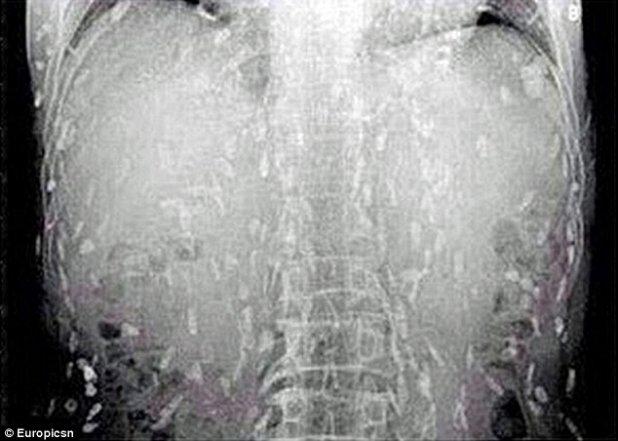

A ajuns la urgenţe cu dureri de stomac şi o senzaţie de mâncărime pe întreg corpul. Ce au descoperit medicii în corpul său i-a lăsat fără cuvinte

Foto: Europicsn